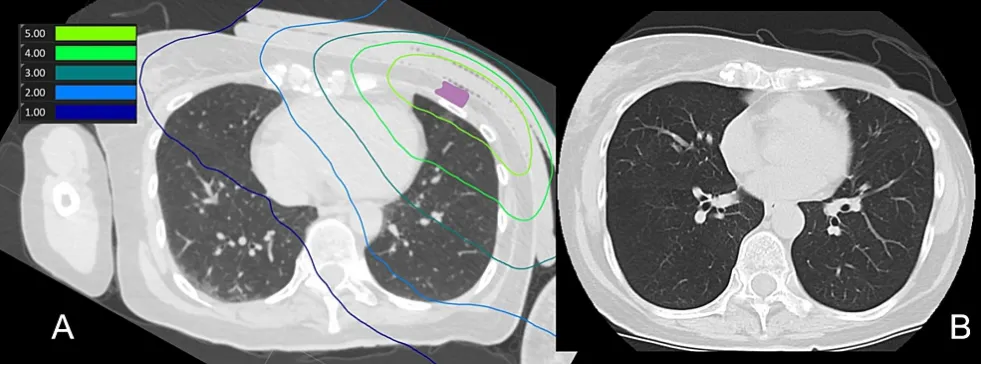

該患者在BNCT治療前有6年以上的左側(cè)乳腺癌化療史,隨后進(jìn)行了乳房切除,并對(duì)左側(cè)胸壁區(qū)域進(jìn)行了30次放射治療,總劑量為54Gy。首次放療三年后左胸復(fù)發(fā),通過手術(shù)、放療和化療進(jìn)行了治療。再次復(fù)發(fā)時(shí),進(jìn)行了BNCT治療。最低處方劑量為23.6Gy-Eq,同側(cè)肺的平均劑量為2.7Gy-Eq。在BNCT治療后第1、3、7、30、60和90天進(jìn)行了CT掃描,結(jié)果均未發(fā)現(xiàn)放射性肺炎跡象。圖2為肺部劑量分布以及治療90天后的CT掃描結(jié)果。

(A) BNCT(肺)劑量分布圖。紫色表示腫瘤總體積

(B) 治療后90天CT掃描,未見放射性肺炎征象,且腫瘤總體積縮小